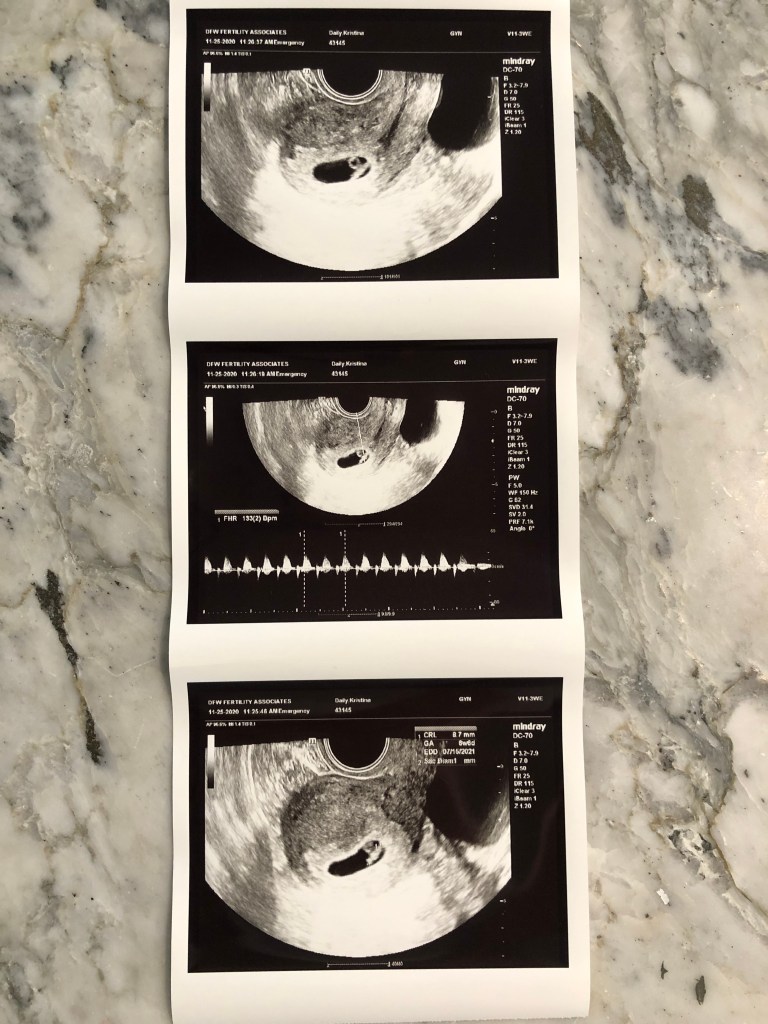

For the first 7 or 8 weeks everything went smoothly. I felt good, had no morning sickness, and when we heard the heartbeat we were sure everything would be just fine. In the middle of the 8th week of pregnancy I experienced some mild spotting, but ultrasound showed our baby thriving with tiny little arm and leg buds and a healthy heartbeat. We were beyond relieved.

Unfortunately, just a few days later, in early January I began to bleed and our pregnancy took a very scary turn. I was diagnosed with a Subchorionic Hematoma and I bled heavily for about a week. Our care team assured me everything would be ok, but I was worried. Our baby was still thriving and it was explained to me that most people go on to have a healthy pregnancy following a Subchorionic Hematoma. I was nervous and determined to listen to our doctors and trust that everything would be ok. And it was… for a little while.

At 14 weeks our ultrasound was perfect! They said the Subchorionic Hematoma had resolved and our daughter was on track. Watching her wiggle around in there was so wonderful. She had quite the personality already.